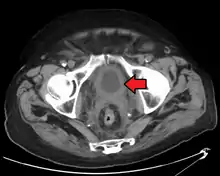

The most common sites for bladder cancer metastases are the lymph nodes, bones, lung, liver, and peritoneum.[78] The most common sentinel lymph nodes draining bladder cancer are obturator and internal iliac lymph nodes. The location of lymphatic spread depends on the location of the tumors. Tumors on the superolateral bladder wall spread to external iliac lymph nodes. Tumors on the neck, anterior wall and fundus spread commonly to the internal iliac lymph nodes.[79] From the regional lymph nodes (i.e. obturator, internal and external lymph nodes) the cancer spreads to distant sites like the common iliac lymph nodes and paraaortic lymph nodes.[80] Skipped lymph node lesions are not seen in bladder cancer.[79]

- N1 Metastasis in a single lymph node in true pelvis (hypogastric, obturator, external iliac, or presacral nodes)

- N2 Metastasis in multiple lymph nodes in true pelvis (hypogastric, obturator, external iliac, or presacral nodes)

- N3 Metastasis in common iliac lymph nodes